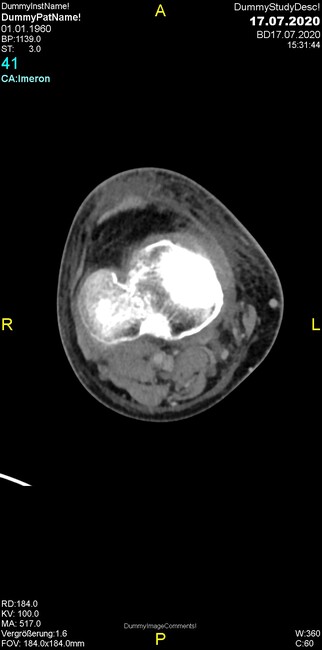

Um welche Modalitäten handelt es sich?

- Röntgen p.a. und lateral, CT coronar Knochenfenster, CT axial Weichgewebsfenster

- Röntgen p.a. und oblique, CT coronar Knochenfenster, CT axial Weichgewebsfenster

- Röntgen p.a. und lateral, CT sagittal Weichgewebsfenster, CT coronar Knochenfenster

- Röntgen p.a. und oblique, CT sagittal Knochenfenster, CT coronar Weichgewebsfenster

- Röntgen p.a. und lateral, CT coronar Weichgewebsfenster, MR axial

Was fällt in der Projektionsradiographie auf?

- Verdichtung im Recessus suprapatellaris

- Aufhellungslinie in Projektion auf die Femurkondylen

- Erhöhter tibialer Slope

- Hypertransparenz tibial

- Subluxationsstellung im Kniegelenk

Was trifft auf den Befund zu?

- Der Befund beschränkt sich auf den Knochen.

- Es besteht hochakuter Handlungsbedarf.

- Der Befund ist tendenziell benigne.

- Der Befund ist tendenziell maligne.

- Der Befund weist einen Zusammenhang zum Patientenalter auf.

Was fällt in der CT im Knochenfenster auf?

- Mediale Gelenkspaltverschmälerung

- Dezente Erosion der fibulären Kortikalis

- Frakturspalt der lateralen Tibiametaphyse

- Weichgewebskalzifikationen lateral angrenzend an den Gelenkspalt

- Osteolyse der Tibiametaphyse unter Beteiligung der Kortikalis

Was kommt differentialdiagnostisch in Frage?

- Kompartmentsyndrom

- Osteomyelitis mit Weichgewebsanteil

- Metastase mit pathologischer Fraktur

- Rheumatoide Athritis

- Posttraumatische Verletzung